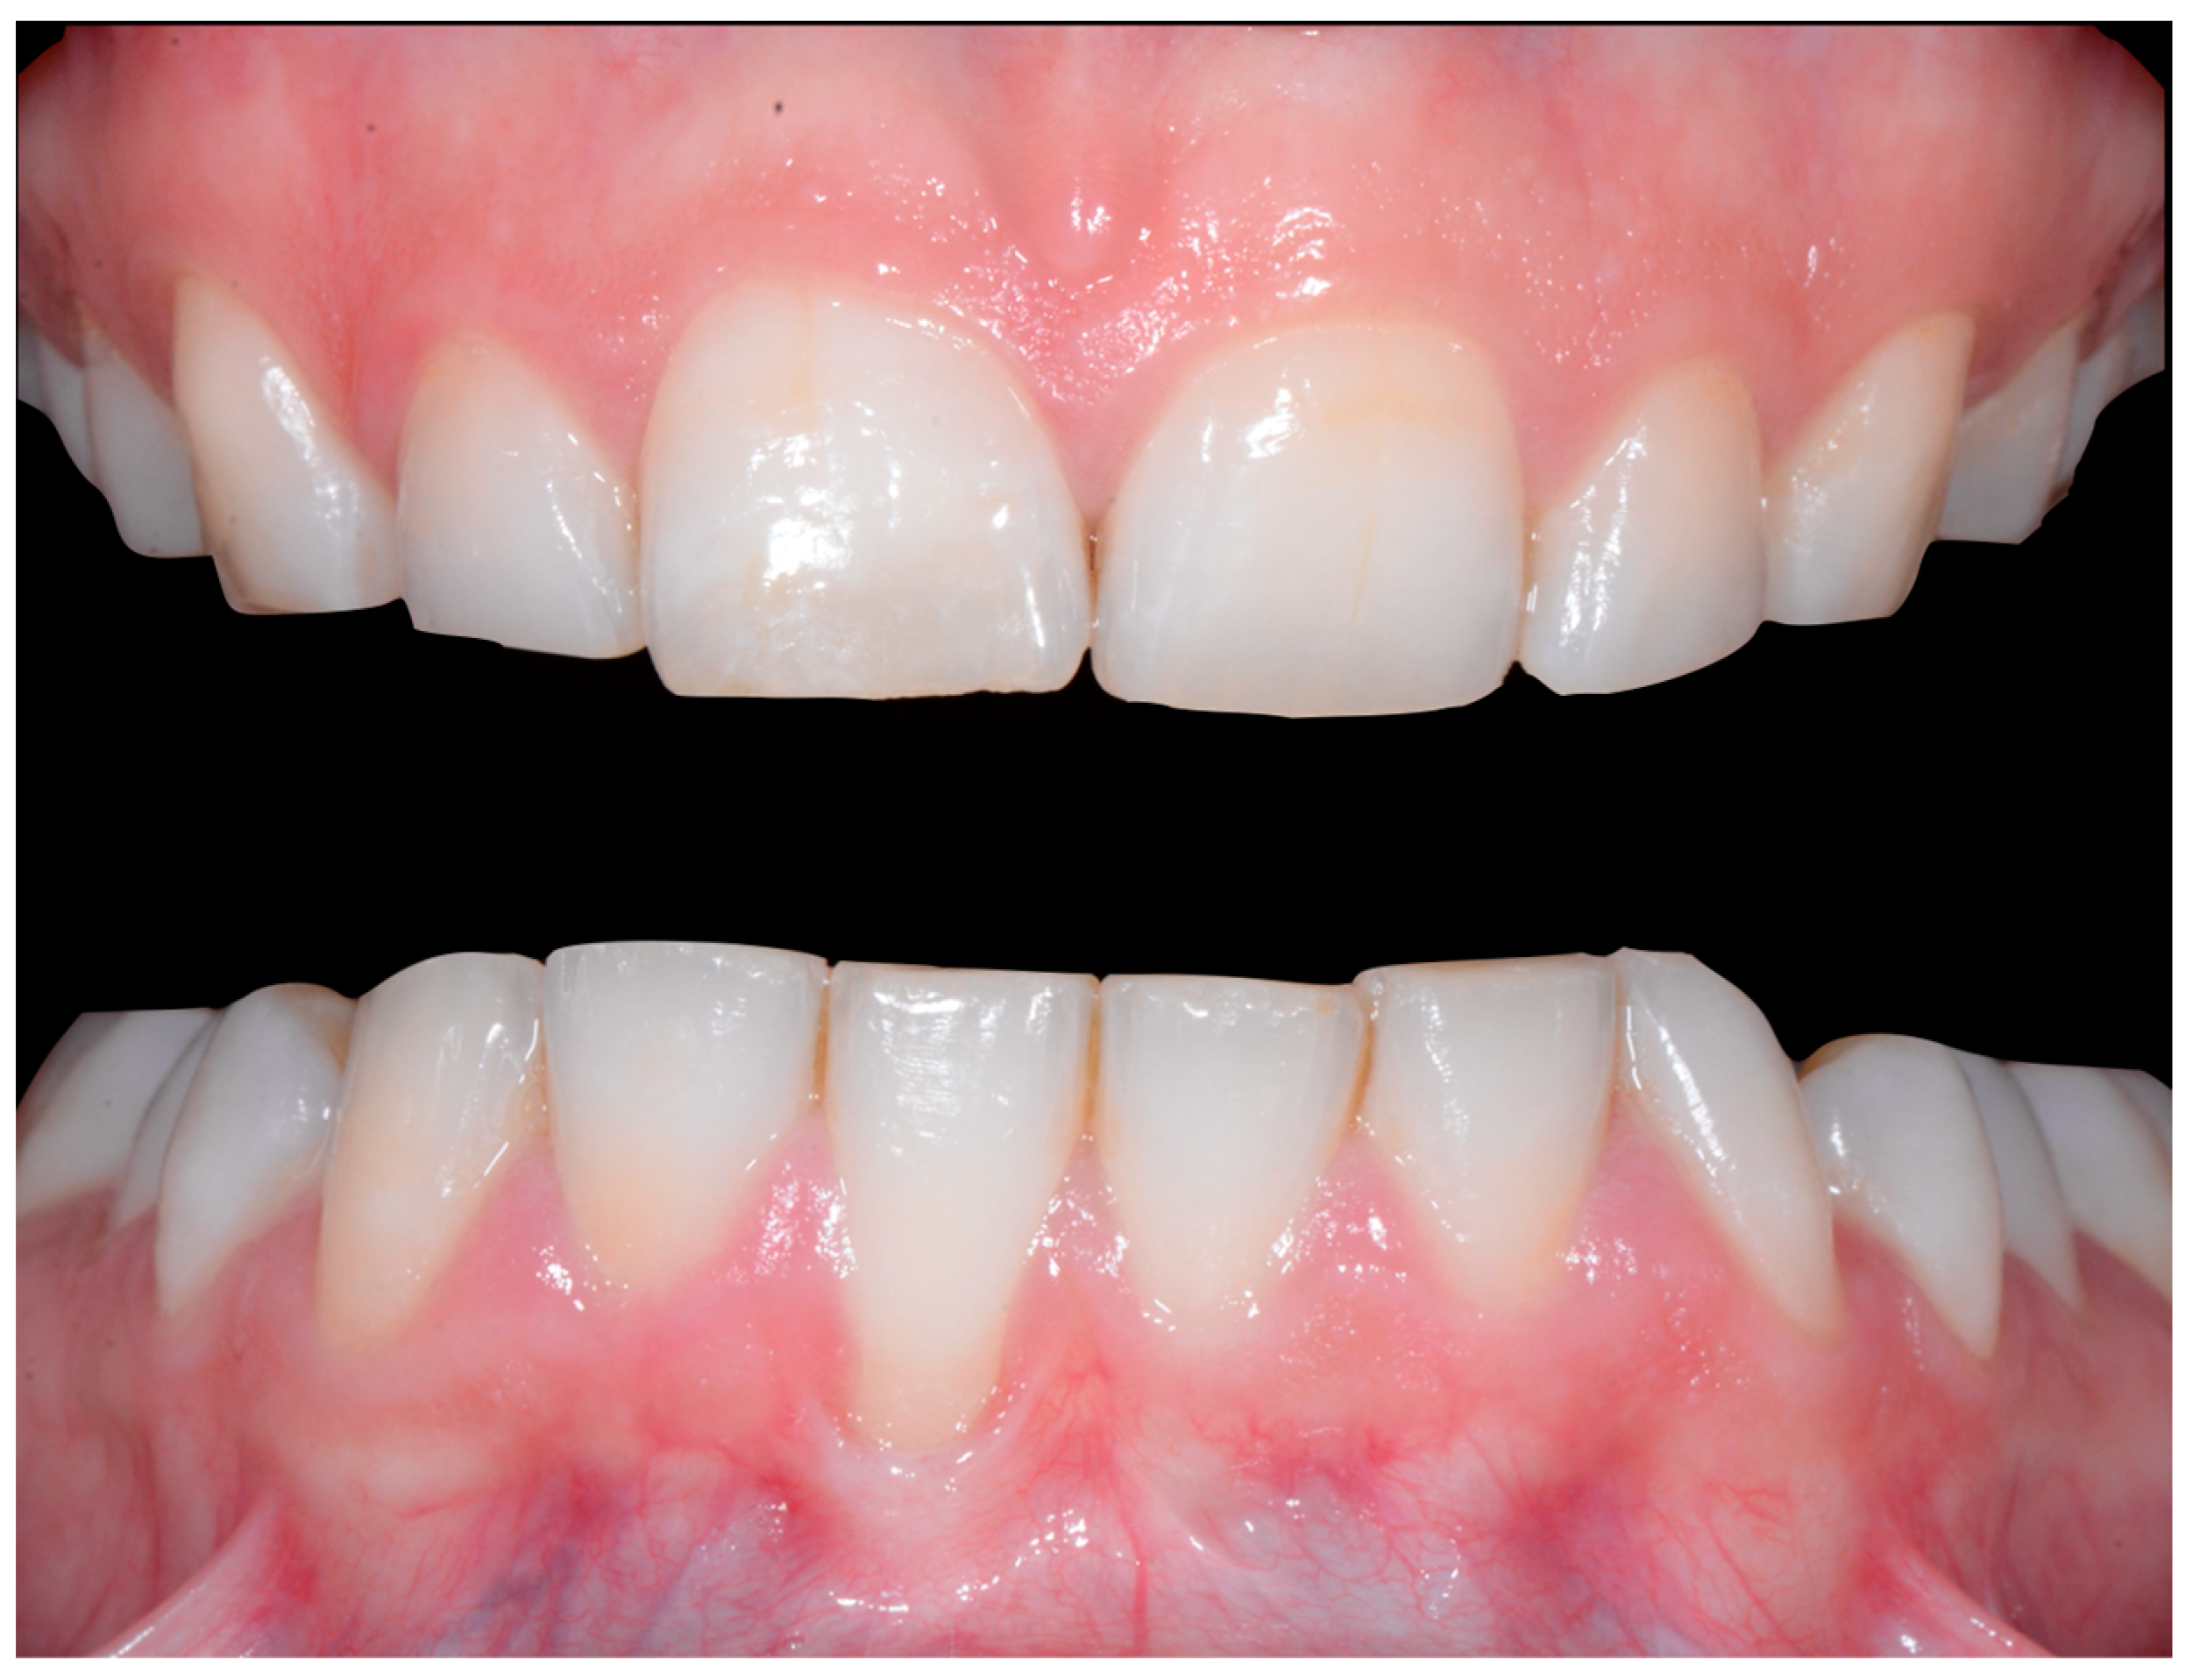

A 26-year-old female patient was referred by her general dentist for suspected wire syndrome. Orthodontic treatment had been performed 10 years previously, and bonded restorations had been fitted at the end of the treatment. The patient mentioned several episodes of breakage/adhesion, without further details. She has good oral hygiene and a right and left Class I (Figure 5).

Intermediate wire syndrome. Frontal and lateral views.

In Figure 6, 11 and 21 show a difference in incisal edge height and gingival margin. Tooth 41 shows gingival recession to the muco-gingival junction (Cairo’s RT1) with root visibility. Tooth 33 had a significant lingual tilt (coronal–lingual torque), not symmetrical to tooth 43.

Intermediate wire syndrome. Frontal view.

The root of tooth 21 is visible through the gingiva (Figure 7). Figure 8 shows the extent of gingival recession on tooth 41.

Intermediate wire syndrome. Lateral view.

Intermediate wire syndrome. Lateral views.

The occlusal views provide additional relevant information (Figure 9 and Figure 10). A maxillary retainer was present on 11 and 21 only and a difference in visibility of the vestibular surfaces (differential torque) on these same teeth was noted.

Intermediate wire syndrome. Occlusal view.

In the mandible, the retainer was broken distal to 42 and, despite being intact on 33, this tooth had increased visibility of its vestibular surface compared to its contralateral tooth (differential torque). Finally, teeth 31 and 41 also showed a difference in the visibility of their vestibular surfaces (differential torque). Ultimately, the patient was diagnosed with an X-effect wire syndrome on 21, an X-effect wire syndrome on 41, and a Twist-effect wire syndrome on 33.